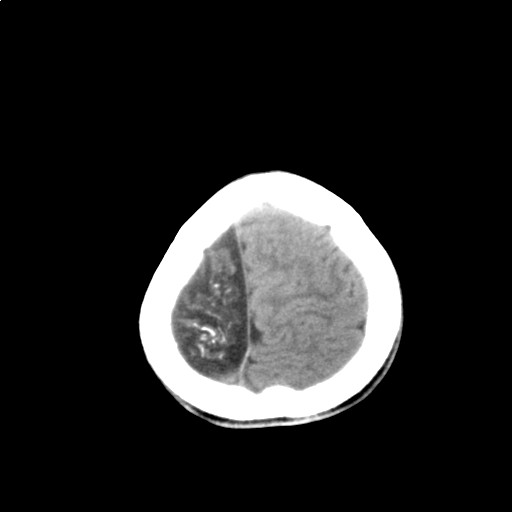

标题: PED3416:F,12Y,智力下降,学习成绩差,8个月时发过高烧。

右侧半球萎缩,软化,多量脑回样钙化,考虑颅面血管瘤病,建议dsa检查

右侧半球萎缩,软化,多量脑回样钙化,同侧颅盖板障增宽,考虑颅面血管瘤病,建议dsa检查与化脓性脑膜炎后遗改变鉴别。